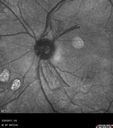

76 year old man with PDR in the left eye. This initially regressed after PRP one year ago but then worsened and regressed again with second PRP. IR images show NVD very nicely

Proliferative Diabetic Retinopathy - NVD regressed with PRP laser596 views76 year old diabetic man - Presented one year ago with NVD in the left eye. This regressed with laser but then a year later worsened. Additional PRP was done and the NVD regressed again.00000